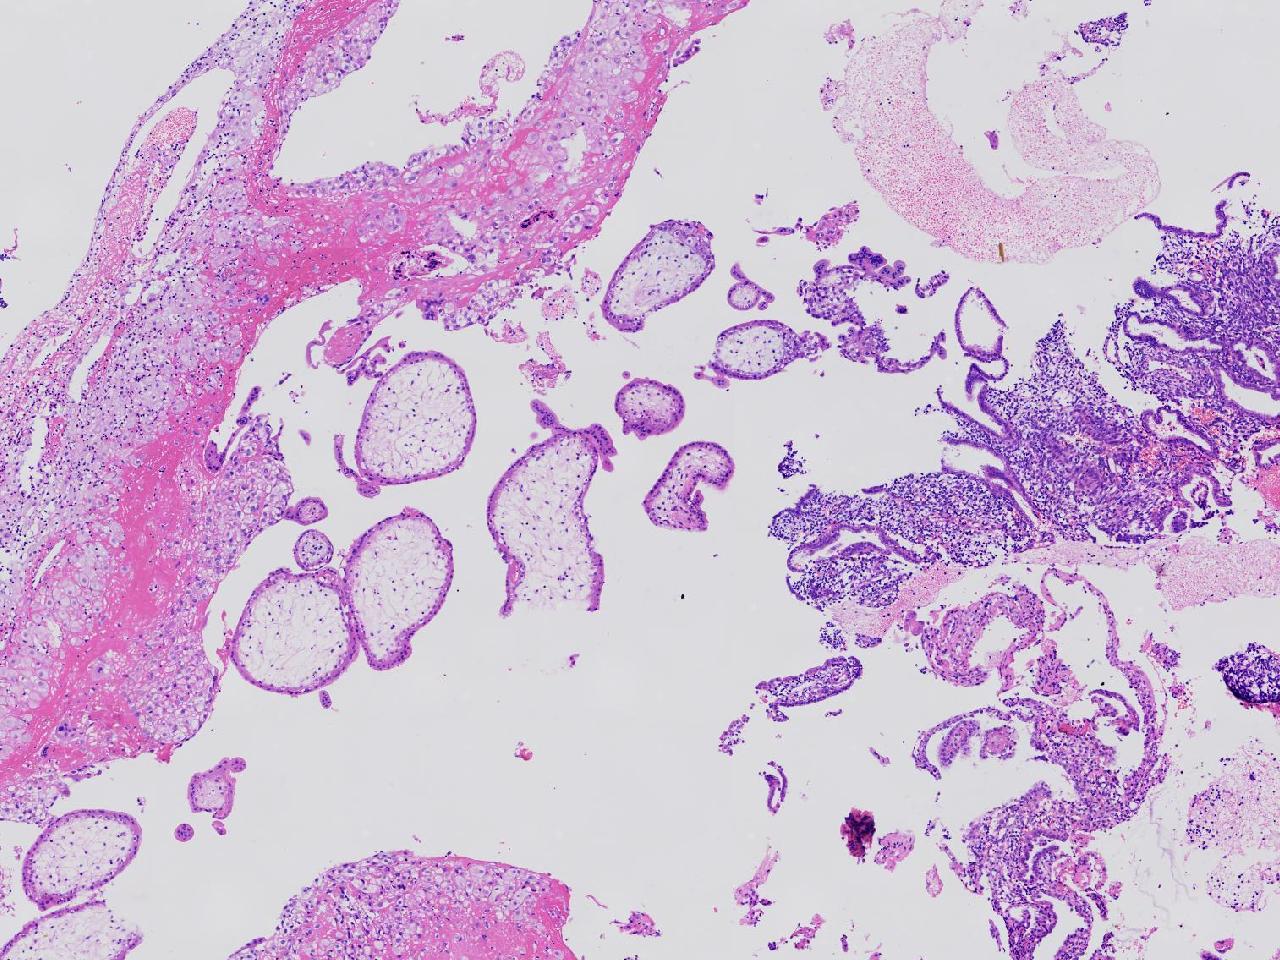

女,29岁,药物流产20余天,阴道少量出血20余天。行诊刮术。

宫腔内容物

灰粉色不整形软组织多块,4X3X3厘米,部分为血凝块。

送检组织为胎盘绒毛及蜕膜组织及滋养层细胞考虑为不全流产